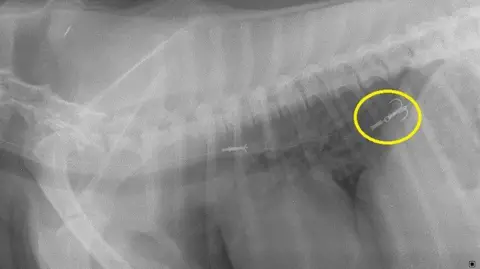

They treated three dogs for fish hook injuries in just one month - including a spaniel called Chip from Stranraer.